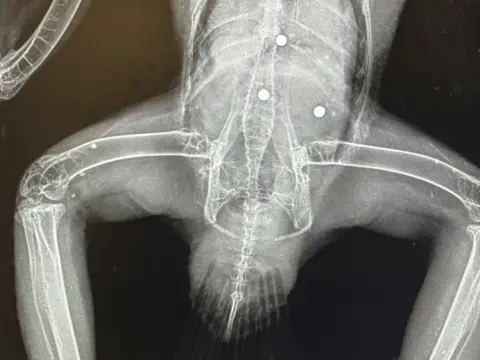

The BBC was also shown X-rays of a buzzard and a seagull which were killed and a Canada goose which survived following surgery. Large ball bearings, embedded into their bodies, are visible on the images.

Det Con Flint said the sizes of the projectiles were "clearly consistent" with a catapult attack.

"I can't think of another weapon that could deliver a ball bearing that size," he said.